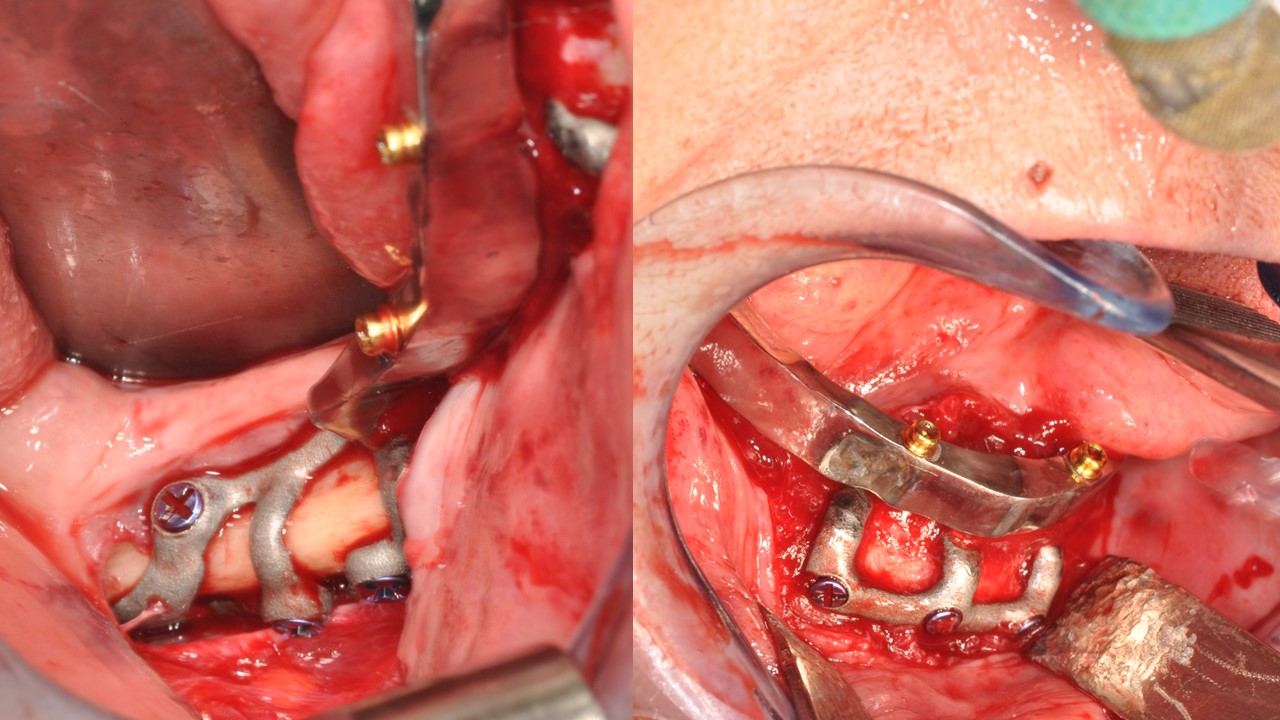

Intervento chirurgico in narcosi con intubazione naso tracheale

Dopo infiltrazione del campo operatorio con Carbocaina 2% e vasocostrittore, si praticano 2 incisioni speculari in regione retromolare al fornice mandibolare ed una sinfisaria dalle sedi di 33 a 43. Viene praticata la scheletrizzazione della sinfisi, rimanendo a distanza dallo sfioccamento delle emergenze mentoniere e delle facce esterne, superiori ed interna fino alla linea miloioidea degli angoli mandibolari. A questo punto viene posto a dimora l’impianto tripodale e ne viene constatato il perfetto fitting osseo. Vengono dunque eseguite le osteosintesi per via intraorale posizionando le viti negli occhielli predisposti e, successivamente, le osteosintesi più distali per via transcutanea. Dopo un attento controllo dell’emostasi è stata eseguita la sutura a strati in Vicryl 3.0 (fig. 6, 7). La parte protesica del caso è stata eseguita dal Dr. Mario Castiglioni (fig. 8, 9). È stato eseguito un controllo a 9 mesi: si constata una perfetta stabilità del dispositivo iuxta osseo (fig. 10) ed una completa guarigione e salute dei tessuti.

Posizionamento delle viti autofilettanti

Fig. 6. Posizionamento delle viti autofilettanti.

Controllo intraoperatorio del fit

Fig. 7. Controllo intraoperatorio del fit.